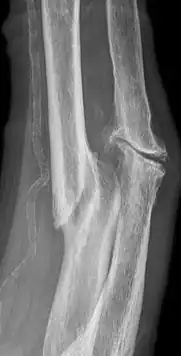

Pseudarthrose (aus altgriechisch ψευδής pseudes, deutsch ‚falsch‘ und arthros ‚Gelenk‘) bezeichnet die ausbleibende Heilung eines Knochenbruchs oder einer Osteotomie.[1]

Synonyme der Pseudarthrose sind Falschgelenk, Scheingelenk und Pseudogelenk. Wenn die Frakturheilung durch Knochenneubildung[2] in einem Zeitraum von vier bis sechs Monaten nach dem Trauma nicht abgeschlossen ist, wird von einer verzögerten Frakturheilung gesprochen. Dauert die Heilung länger als sechs Monate, spricht man von einer Pseudarthrose. Von einer Pseudarthrose betroffene Knochen sind häufig Schaftbrüche langer Röhrenknochen (Unterschenkel, Oberschenkel, Oberarm und Elle mit Speiche) sowie das Kahnbein.

Pseudarthrosen führen häufig zu dauerhaften Funktionseinschränkungen und anhaltenden Schmerzen. Weitere Merkmale sind abnorme Beweglichkeit und ein Pseudarthrosespalt mit reaktiver Sklerosierung in der Umgebung im Röntgenbild.